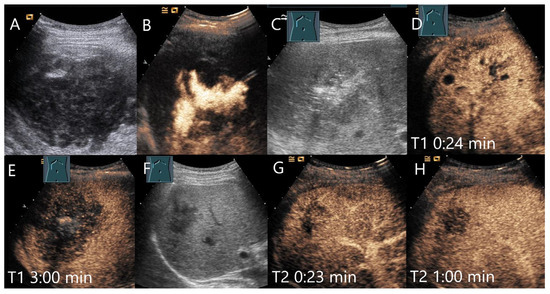

Figure 12.

Female patient with amebic abscess, fever, and general malaise after a stay in northern India. On B-mode US, a 90 × 65 mm large liquid hypoechoic, well demarcated FLL (A). The abscess was relieved by drainage and the position was checked by intracavitary CEUS (B). After complete drainage of the liquid contents, a hypoechoic lesion remained (C). The liver tissue surrounding the heterogeneous enhanced lesion showed a large area of arterial isoenhancement after 24 s (D). The lesion is hypoenhanced after 3 min with hyperenhanced surrounded parenchyma (E). Serology revealed an elevated amebic titer. Under appropriate therapy, regression occurred after 4 weeks (F). However, the lesion showed a hypoenhancement after 23 s (G) and progressive washout after 1 min (H).